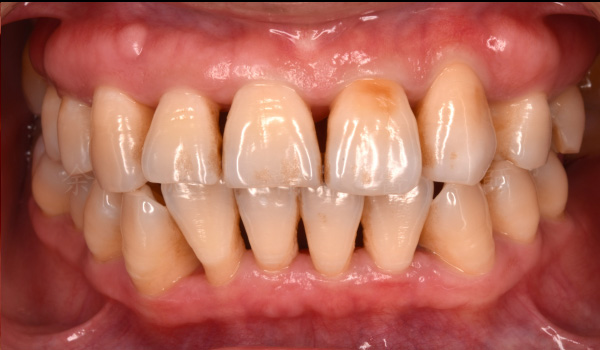

牙周治療前

嚴重牙結⽯堆積,反覆牙齦腫痛,⾃發性的牙齦出⾎。

牙周治療後

徹底清除牙菌斑與牙結⽯,牙齦恢復健康。